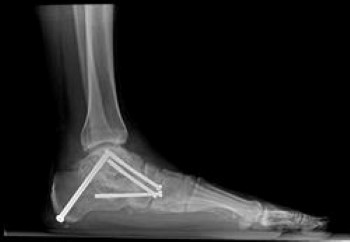

Fusion

This X-ray shows a very stiff flatfoot deformity. A fusion of the three joints in the back of the foot is required and can successfully recreate the arch and allow restoration of function.